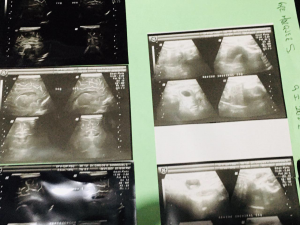

Mia Guadalupe, de tan sólo 3 meses de edad enfrenta este padecimiento después de su nacimiento, tiene una hernia inguinal de lado  izquierdo.

izquierdo.

A falta de esta intervención la pequeña podría empeorar de su estado de salud, por lo que los diagnósticos médicos le indican a la a madre que debe ser operada lo más pronto posible.